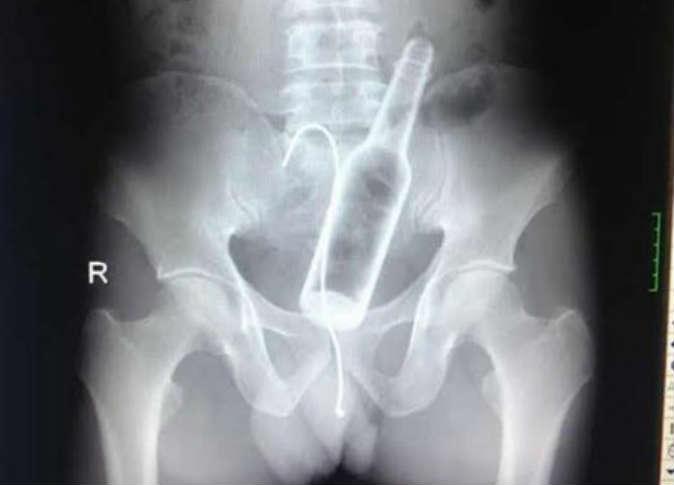

أجرى أطباء صينيون أشعة سينية لمريض كان يشكو من آلام مبرحة في بطنه، ليكتشفوا وجود زجاجة راكدة بها، وهو ما لم يجدوا له تفسيراً لدى المريض نفسه..

وبعد أن أطلع الأطباء المريض، الذي لم يرغب في الكشف عن هويته، على صور الأشعة، أدلى بملابسات وصولها إلى أمعائه، بعد أن جلس عليها عن طريق الخطأ، موضحاً أنه حاول استخراجها بسلك عن طريق الفم، لكنه لم ينجح، خاصة بعد أن سقط السلك في بطنه أيضاً، مما دفعه إلى زيارة طبيب..

وخضع المريض إلى جراحة لاستخراج السلك والزجاجة، التي تسببت له في بعض الجروح الداخلية بالأمعاء، حسبما ذكرت صحيفة "ميرور" البريطانية